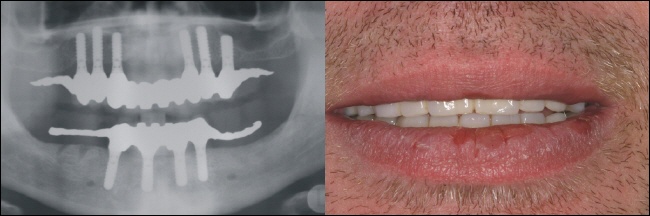

Die fertige Arbeit ermöglicht auf den sechs Teleskopen im Oberkiefer eine rein kieferkammbegrenzte, also gaumenfreie Versorgung. Das Röntgenbild links zeigt die solide Konstruktion, die eine reine Kaukraftweiterleitung in den Kieferknochen ermöglicht. |

Auch im Unterkiefer ist der Zahnersatz auf den Kieferkamm begrenzt und ermöglicht so höchsten Tragekomfort. |